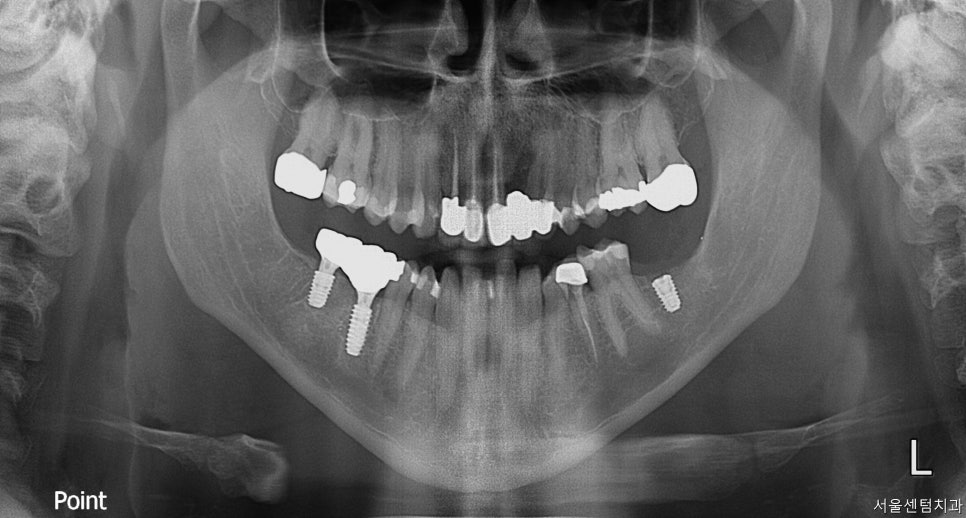

바로 파노라마 촬영을 진행하였습니다.

문제가 있던 치아는 #46번 치아는 깨져서 오셨고

#47번은 안좋아서 이미

발치 하신지 좀 되셨다고 하셨습니다.

반대편 #37번도 안좋아서 발치 하셨는데

계속 치아가 없는 상태로 있다보면

그 위에 맞닿아 있는 #17번 #27번 치아도

내려올 수 있는데 이미 조금 정출되어 보여

빨리 임플란트를 하시는 걸로 얘기드리고 당일날

바로 수술 진행하였습니다.

엑스레이 상에 보이는 것처럼 오른쪽 아래

#46 #47번은 힐링으로 지금 되어 있어

잇몸밖으로도 힐링이 보이고

#37은 커버스크류로 되어 잇몸 안에 있어

간혹 환자분들이 식립 후에 입안에서

안보이신다고 하시기도 합니다.

그래서 수술이 끝나고 엑스레이 촬영을 다시 하여

수술 성공 여부와 환자분께 확인시켜드리려

다시 한번 설명드리고 있습니다.